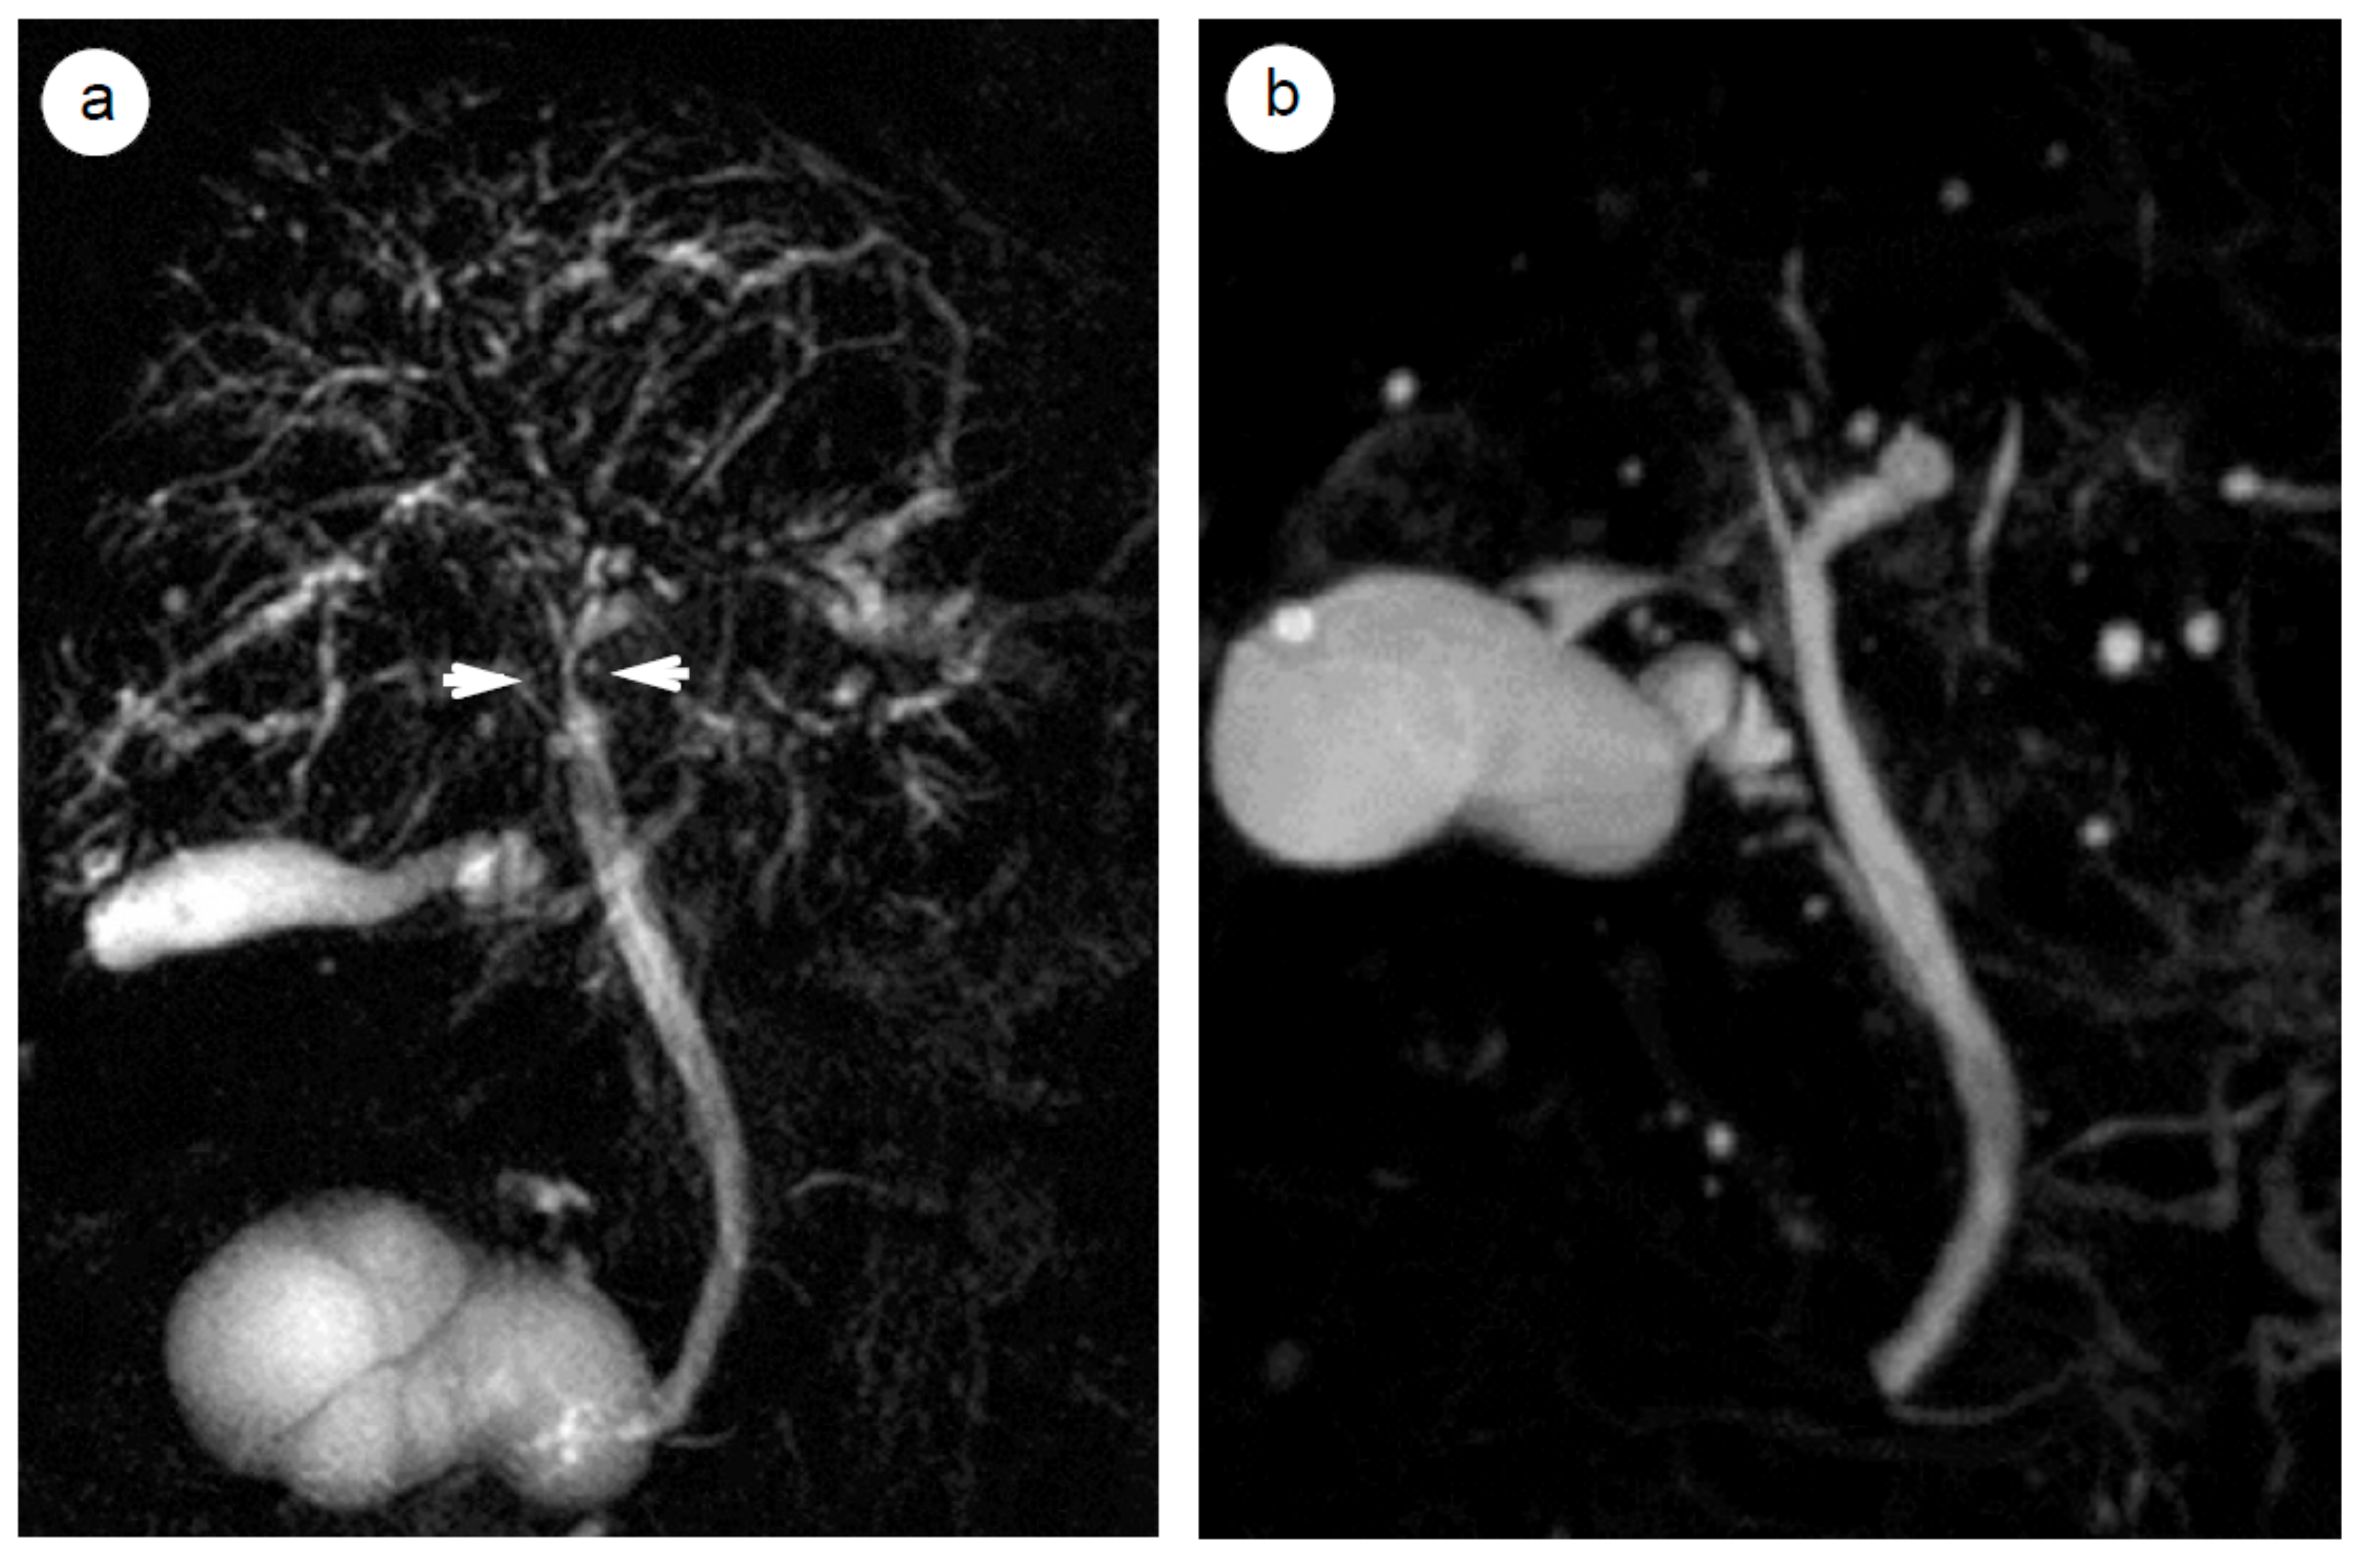

- Ishikawa, T.; Itoh, A.; Kawashima, H.; Ohno, E.; Itoh, Y.; Nakamura, Y.; Hiramatsu, T.; Miyahara, R.; Ohmiya, N.; Haruta, J.; et al. Peripancreatic vascular involvements of autoimmune pancreatitis. J. Gastroenterol. Hepatol. 2012, 27, 1790–1795. [Google Scholar] [CrossRef]